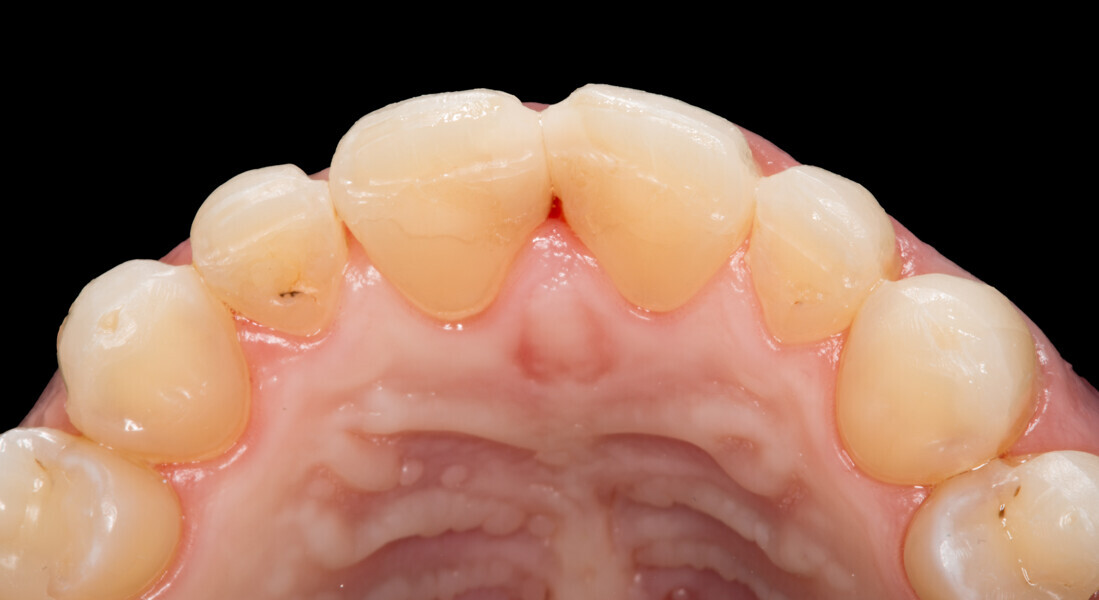

Fig. 1: Initial clinical situation.

Fig. 2: Initial clinical situation.

Fig. 3: Initial clinical situation.

Fig. 4: Initial clinical situation.